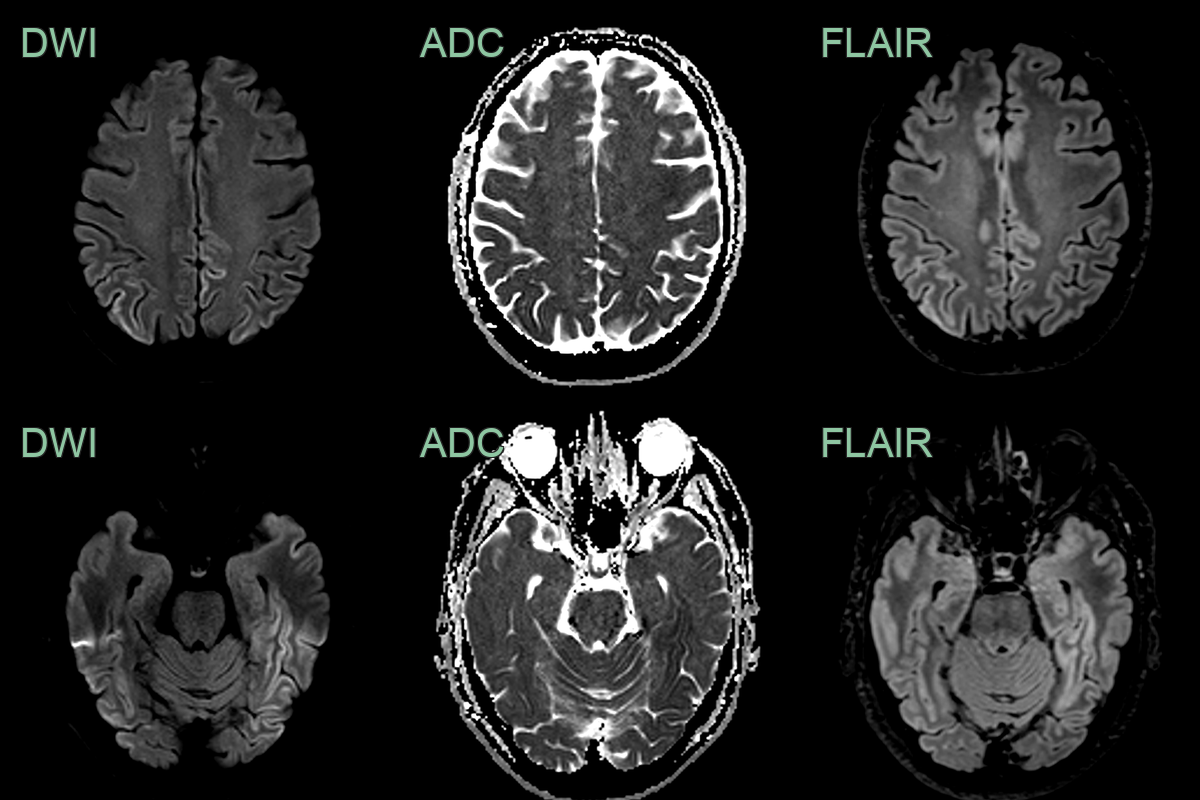

- DWI/FLAIR:

- Cortical ribboning (high signal in cortical grey matter)

- Basal ganglia hyperintensities (caudate and putamen)

- Thalamic hyperintensities (pulvinar sign in vCJD)